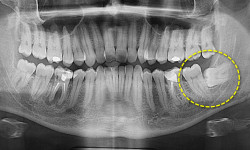

хірургічна процедура, спрямована на відновлення або збільшення об'єму кісткової тканини. Вона використовується, коли кістка пошкоджена або втрачена через травму, хворобу або необхідність імплантації зубів

Процес підсадки кістки:

1. 1. Визначення обсягу дефекту:

Лікар оцінює розмір та розташування дефекту кісткової тканини.